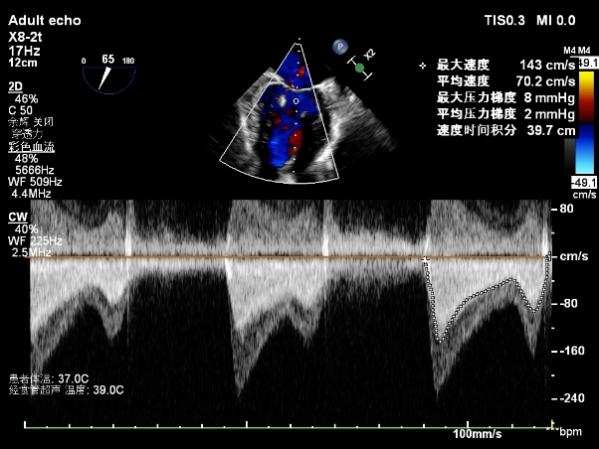

与患者及家属充分沟通并征得同意后,手术如期举行。术中在食道超声引导下,王正忠团队凭借精湛的介入操作技术,从下腔静脉右房到左房穿刺房间隔,手术先后下了3个二尖瓣夹合装置,精准夹合重度脱垂反流的二尖瓣,手术效果立竿见影,食道超声显示夹合组织充分,二尖瓣反流量由重度(4+)降至微量(1+)。术后随访患者恢复良好,心功能得到明显改善。

△TEER术后二尖瓣反流由重度变成少量